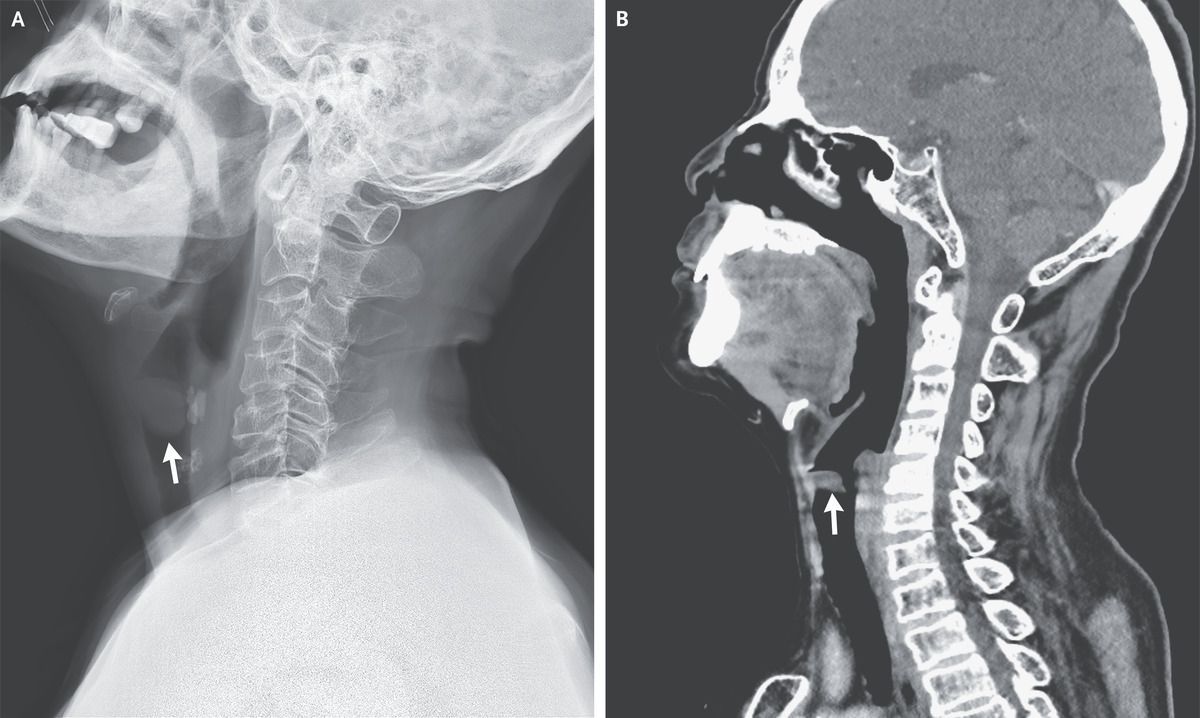

A 69-year-old man presented to the emergency department with a 2-week history of progressive, intermittent dyspnea that worsened when he was lying down. He also reported a 2-year history of hoarseness and a 30-pack-year smoking history. He worked in a noisy factory and frequently yelled to communicate with coworkers. On physical examination, there were normal inspiratory breath sounds and loud expiratory wheezes that were heard best over the neck. Owing to concern for upper-airway obstruction, radiography and computed tomography of the neck were performed, both of which showed a mass causing partial obstruction of the upper airway (Panels A and B, respectively, arrows). Bronchoscopy was subsequently performed, during which a large vocal-cord polyp was found to be causing intermittent airway obstruction in a ball-valve fashion during expiration (see video). Vocal-cord polyps commonly manifest with hoarseness. Such polyps result from chronic irritation of the vocal cords, such as from smoking, reflux, or vocal strain. Immediately after bronchoscopic polypectomy, the patient’s dyspnea resolved. Histopathological analysis confirmed the lesion to be a benign vocal-cord polyp. At the 1-month follow-up, his voice had returned to normal. Counseling on smoking cessation and vocal-strain avoidance was given.